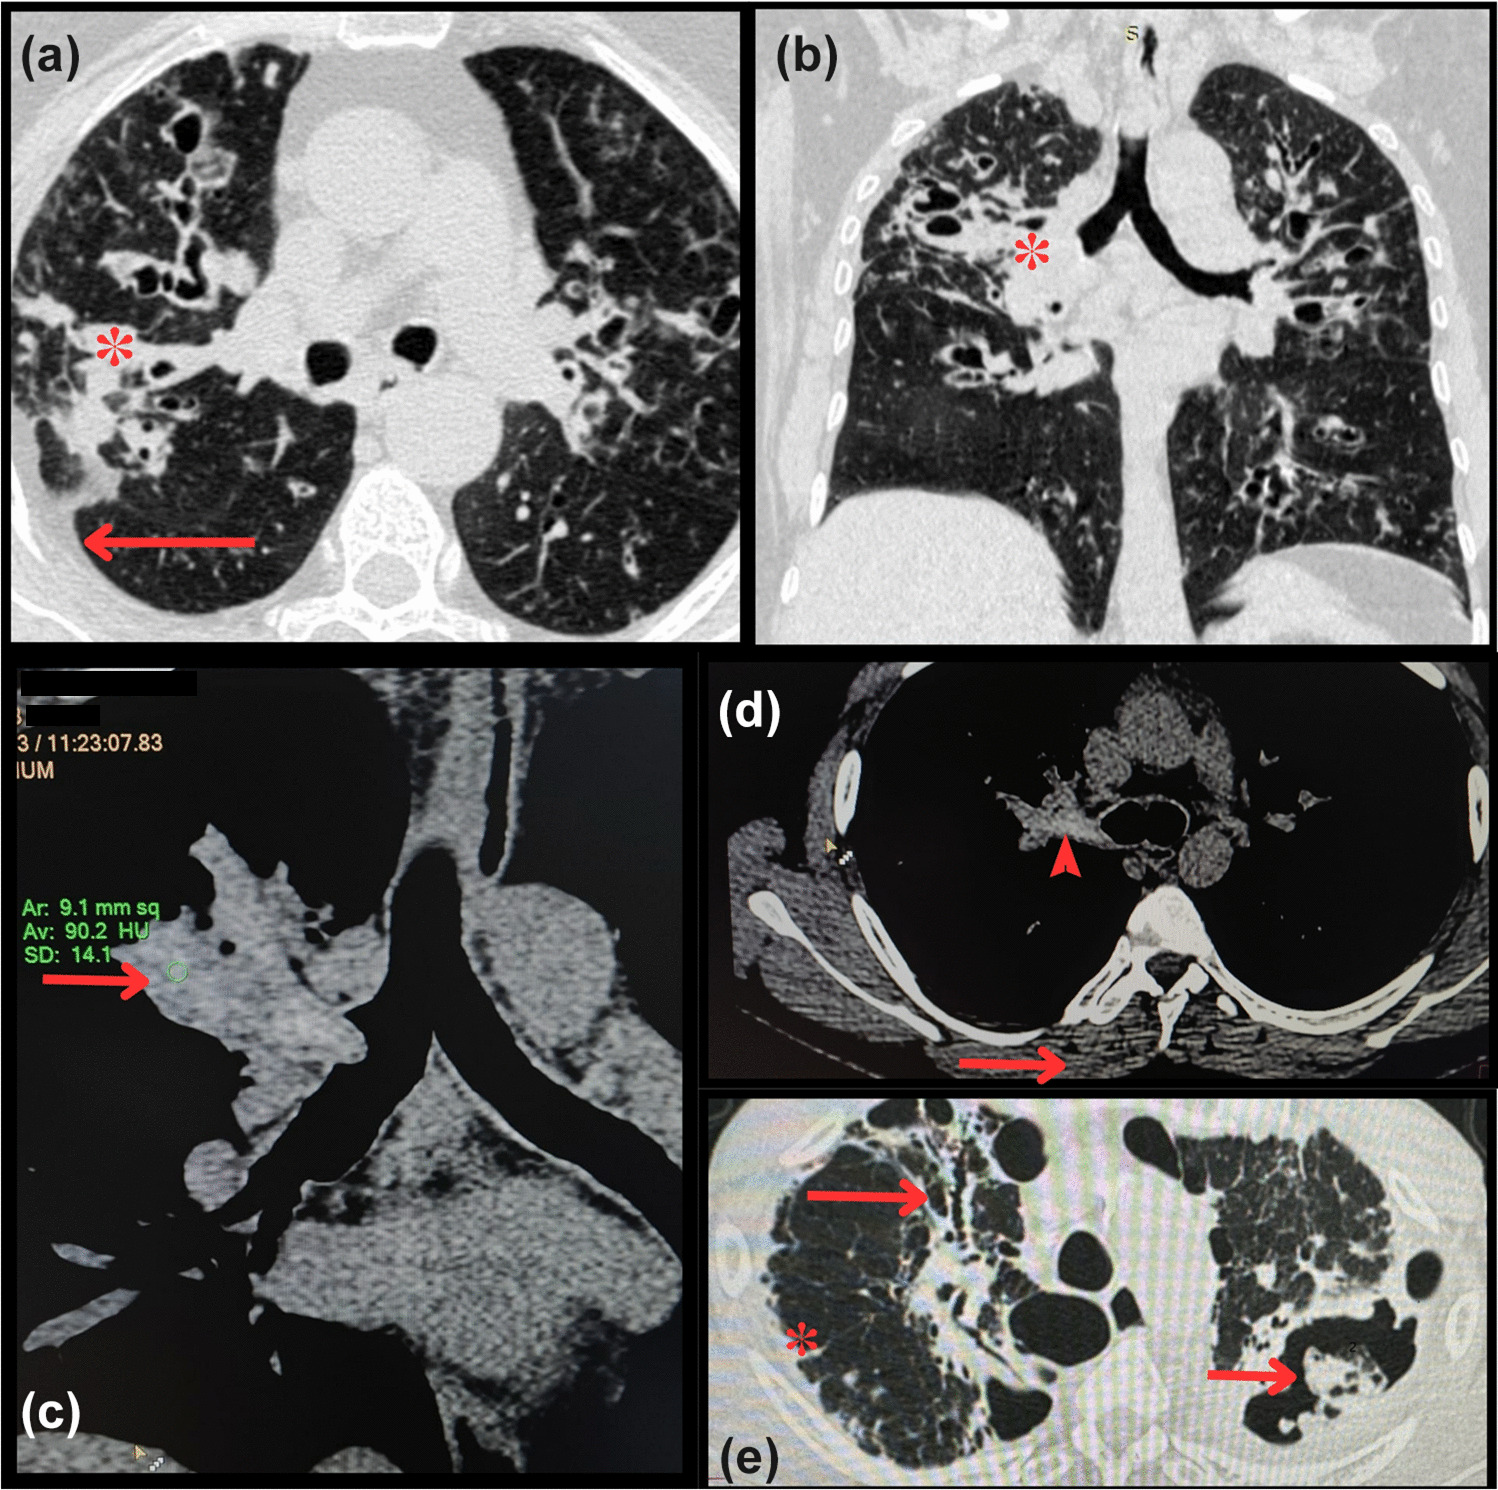

Obstructive sleep apnea (OSA) is characterized by recurrent episodes of complete (apnea) or partial (hypopnea) upper airway obstruction during sleep that causes arousal from sleep and/or a fall in oxyhemoglobin saturation (SpO2) [1] (Fig. 1).

Fig. 1figure 1

A home sleep apnea test recording showing intermittent pauses in airflow (OA) in Supine position with associated drops in SpO2 levels (Desat) and oscillations in the pulse rate. The snoring intensity achieves 100 dB, and breathing efforts during apneas are documented by the thoracic and abdominal belts showing that the apneic events are obstructive. OA, obstructive apneas